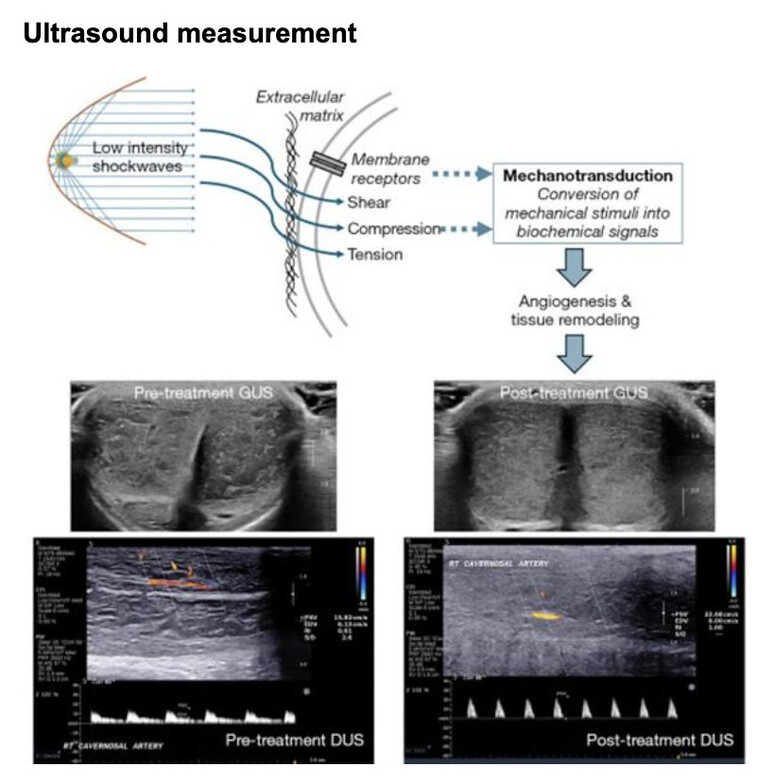

The novel study published in October 2024 by Sue Goldstein, Dr. Irwin Goldstein, and Dr. Noel Kim from the University of San Diego, California, investigated the improvement on erectile tissue quality following Spark Wave application, validating the hypothesis of the multiple beneficial improvements within the penile tissue, and including a novel observation on erectile tissue homogeneity.

The observational study published in July 2024, by Mateo Rubino and colleagues, with the participation of Prof. Carlo Bettocchi from the University of Foggia, Italy; similarly demonstrated an increase in blood flow velocity and improvement in erectile quality in non-diabetic patients. The therapy appears particularly beneficial for patients with mild to moderate vascular erectile dysfunction. Both studies demonstrate that shockwave therapy is a safe, effective, and proven regenerative treatment option in urology.

- Significantly improves erectile function (IIEF)

- Significantly more patients reached an erection that lasted long enough for successful intercourse Objective greyscale ultrasound measurement correlates with erectile function score